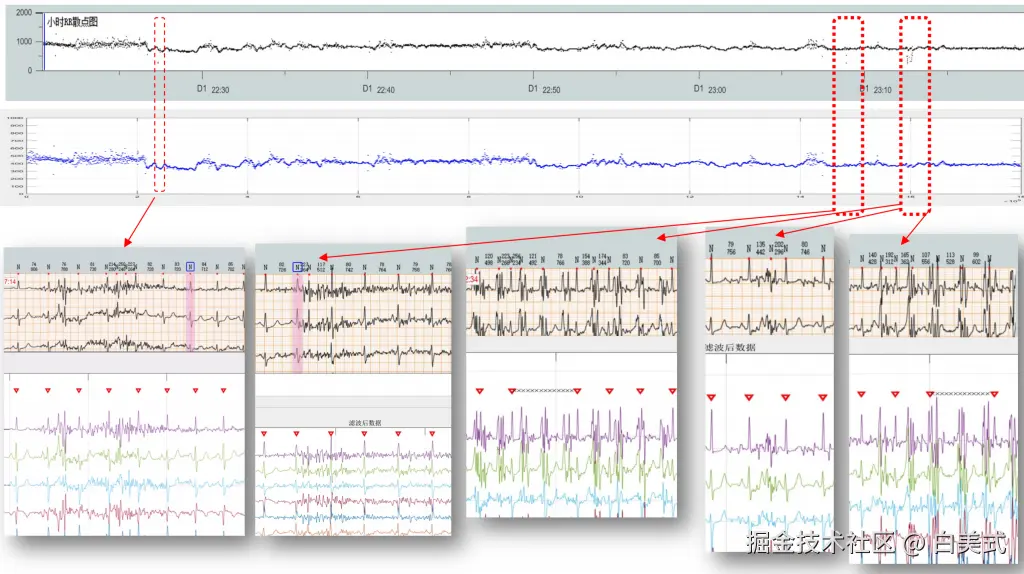

苏州唯理科技发布了自研的24小时12导联心电图ECG的处理与分析算法,包含了信号的预处理,滤波、高鲁棒性的R峰识别、心律失常疾病的分类等Holter所需的算法。算法的实测效果得到了国产器械厂商到一致好评。R峰识别率大幅提升,大大节省了医生的时间。

R峰识别准确率展示